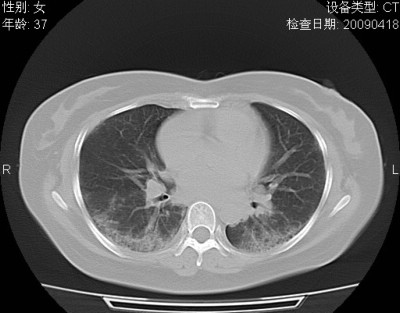

以下是引用随光逐影在2009-4-20 8:03:00的发言:[br]两肺间质性病变(间质性肺炎?特发性肺间质纤维化?)。

以下是引用51736011在2009-4-21 16:24:00的发言:[br]两肺间质性病变(间质性肺炎?特发性肺间质纤维化?)。